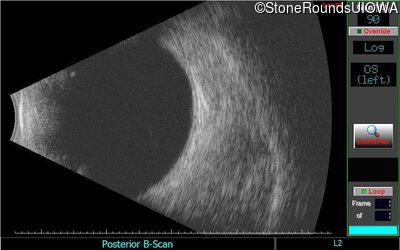

B-Scan Ultrasonography - Left - 20/30 +2

Exemplar